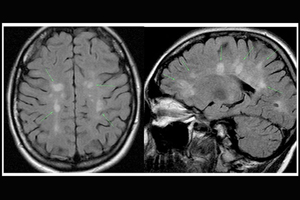

Розсіяний склероз — це хронічне захворювання центральної нервової системи, яке постійно прогресує. Клінічно проявляється неврологічною симптоматикою: розладами зору, патологією рухової активності, порушенням функції тазових органів. Точні причини виникнення розсіяного склерозу невідомі.